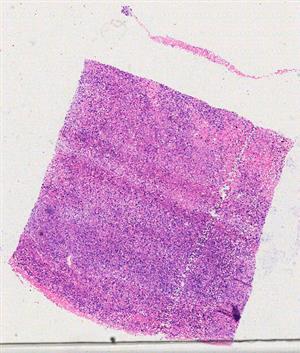

10518 |

右乳 |

女, 50岁, 因“发现双侧乳腺肿块1月”入院。患者1月前发现双侧乳腺蚕豆大... |

上海市同济医院 |

有诊断 |